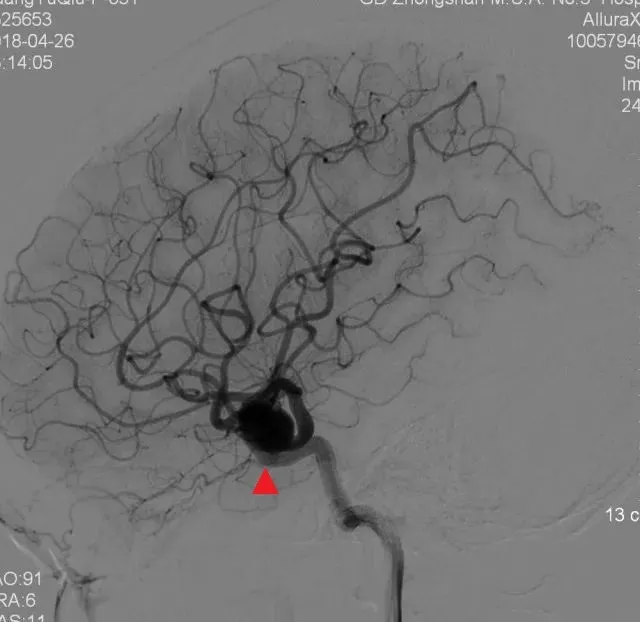

CTA、DSA示:右侧海绵窦段巨大动脉瘤,13*19mm,形状不规则。血常规、凝血、肝肾功、胸片、心电图无异常。

图1. CTA、DSA示:右侧海绵窦段巨大动脉瘤

球囊闭塞实验:球囊闭塞后动脉瘤消失,对侧造影显示前循环开放,患侧大脑中动脉主干及分支显影良好,豆纹动脉显影稍延迟。

图2. 球囊闭塞实验结果